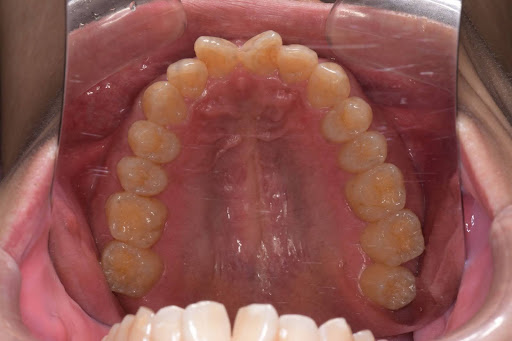

【症例写真】豊富な経験に基づき、歯の重なりやアーチの形状を美しく改善します。

Before